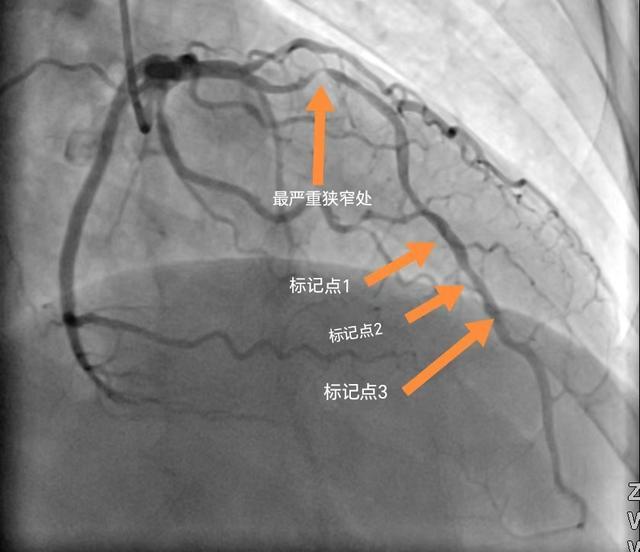

患者曾先生,56岁,于2024年9月10日因“胸腹部疼痛1年,再发10天”入住汉寿县人民医院心血管内科一病区治疗,入院后冠脉造影检查示:冠状动脉严重狭窄病变,其中前降支最严重处狭窄达90%。经朱济文副主任医师率领的心血管内科团队研究讨论,认为患者有冠脉内支架植入术指征。

(冠脉介入治疗前)

为了深入评估曾先生的血管病变情况同时让支架精准定位,在征得患者家属同意后于2024年9月13日为患者实施了冠脉内超声检查+冠脉内支架植入术。